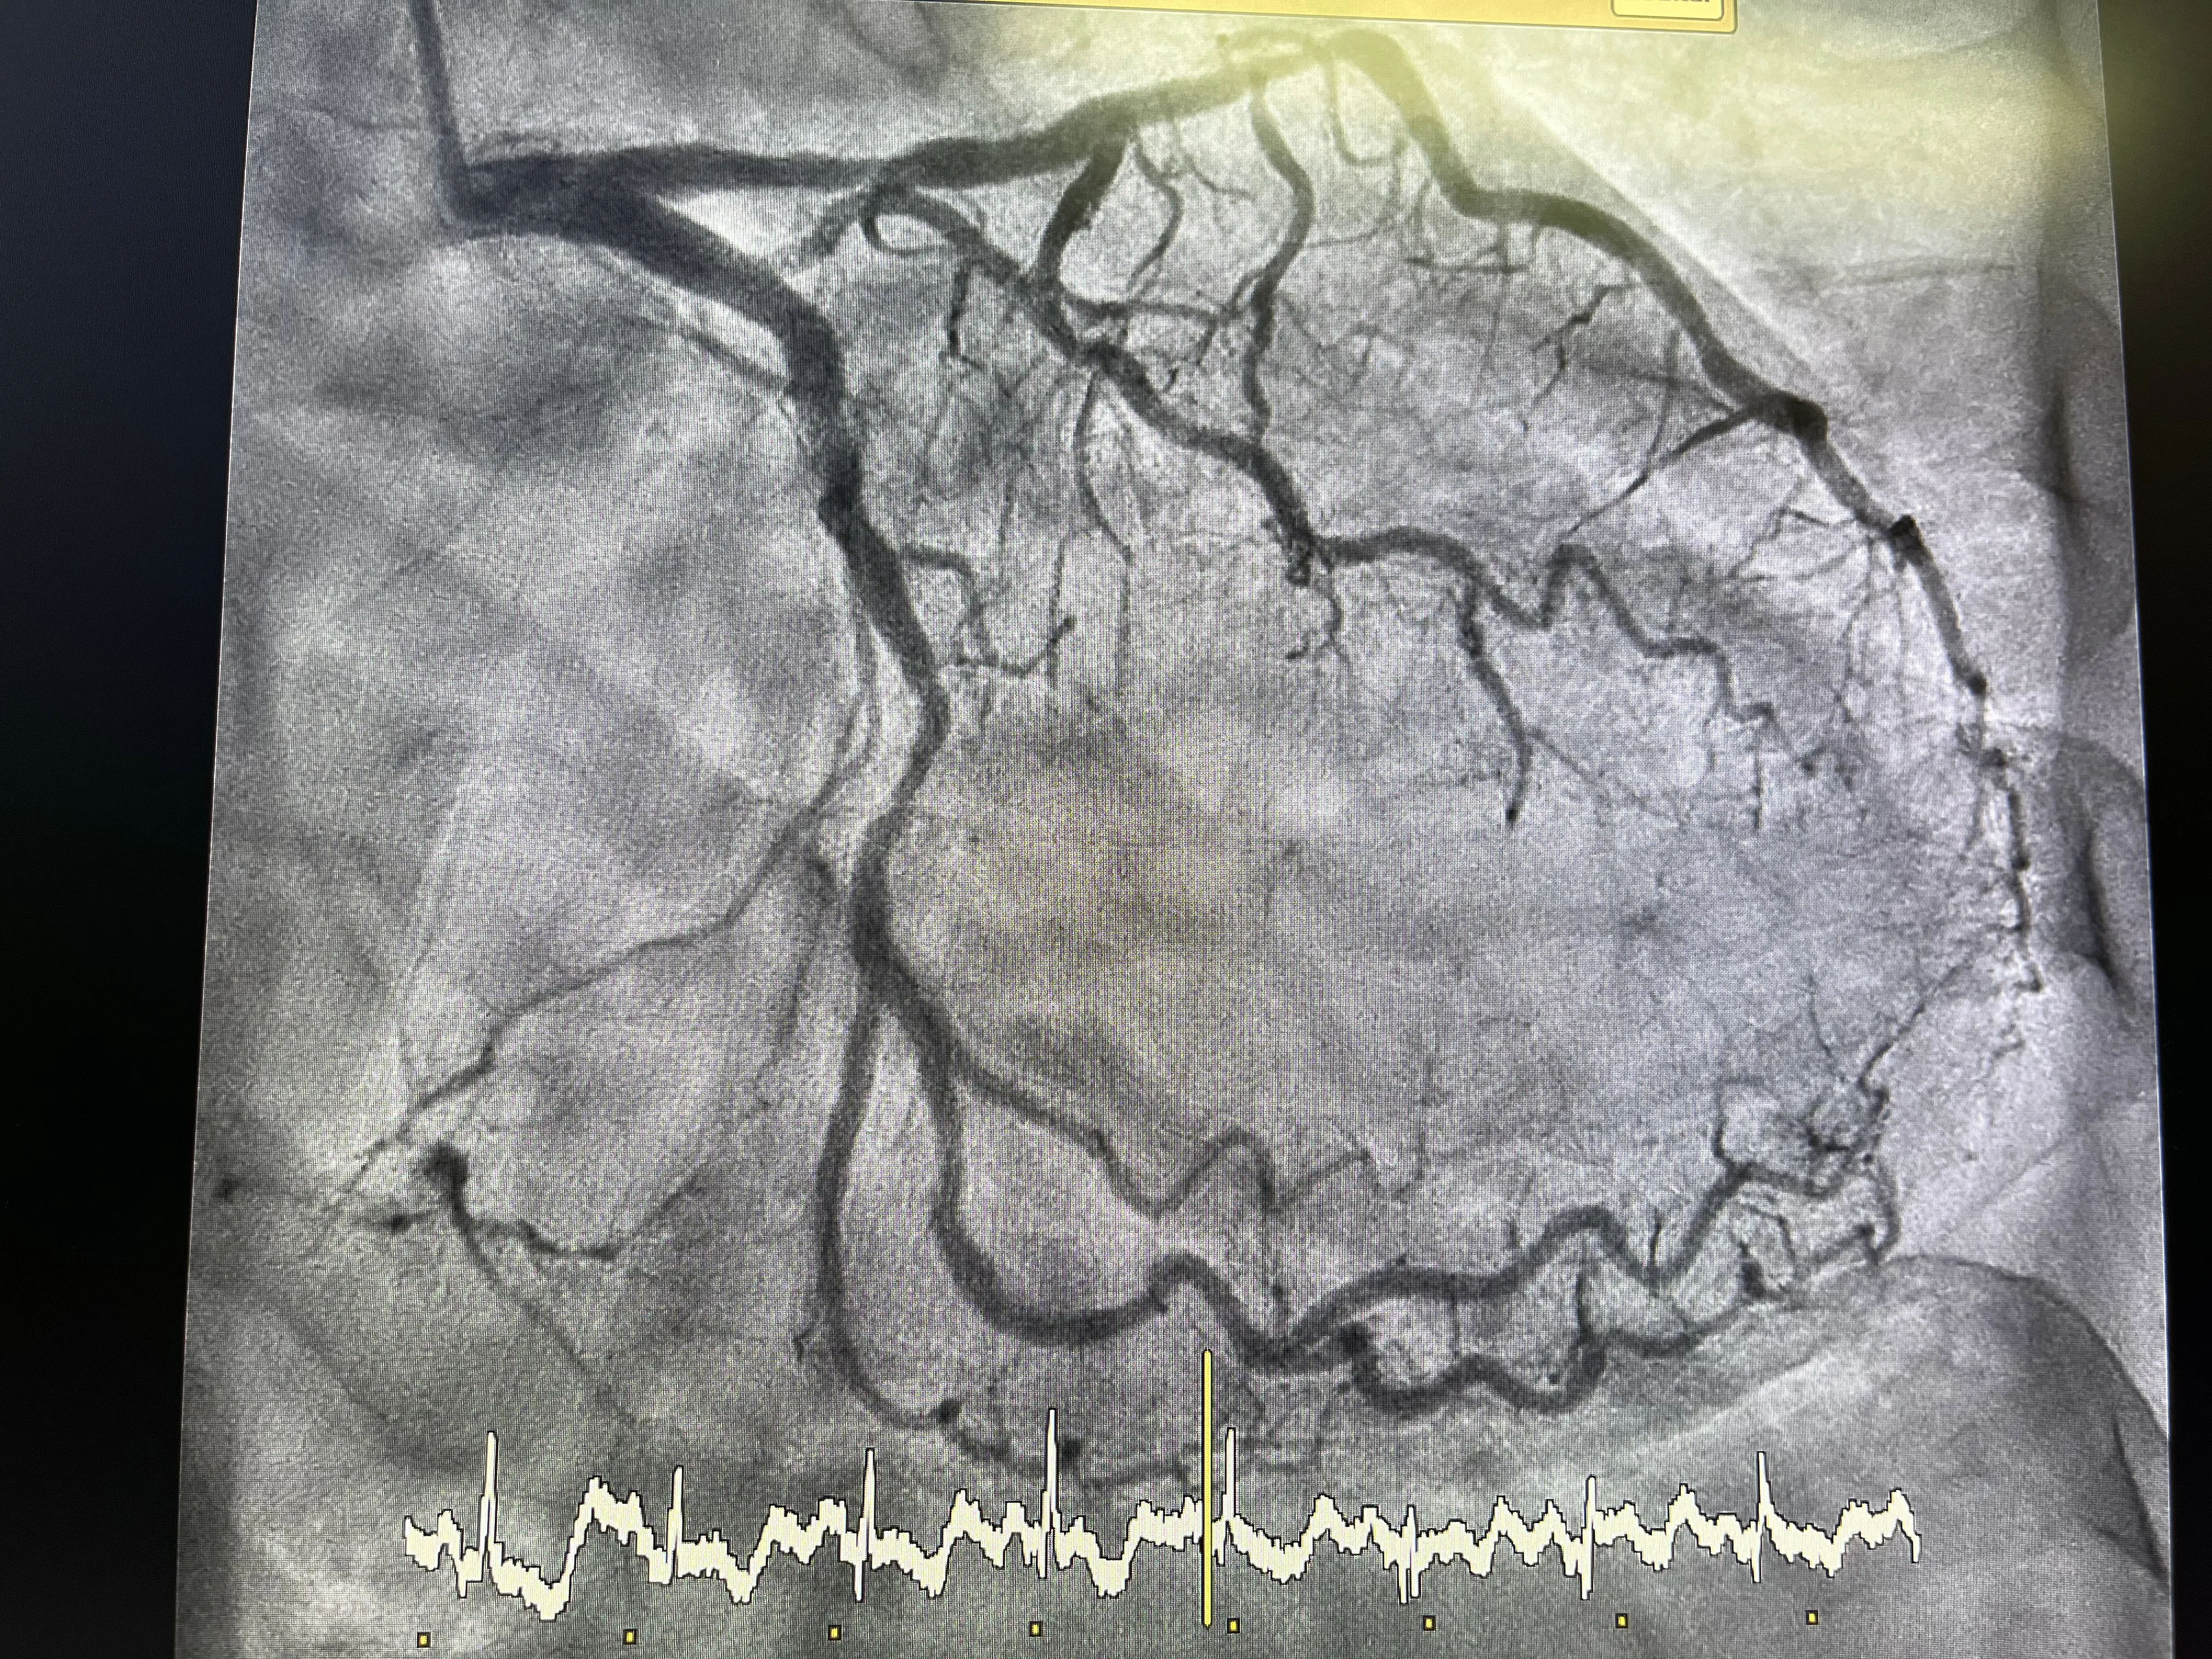

El tercer paso, y probablemente el más decisivo, fue el implante del stent en la coronaria derecha previamente tapada. Con la guía en posición estable y la lesión ya predilatada, se avanzó el stent hasta cubrir completamente el segmento ocluido. Una vez situado en el lugar deseado, se procedió a su expansión mediante inflado controlado, buscando una adecuada adaptación a la pared arterial. El objetivo es conseguir una luz amplia y uniforme, sin zonas de infraexpansión que puedan comprometer el resultado a corto o medio plazo.

Tras el implante del stent, se realizaron nuevas inyecciones de contraste para valorar el resultado angiográfico final. En este caso real, el stent quedó muy bien, con una restauración clara del flujo coronario y sin defectos de repleción significativos. La imagen final mostraba una coronaria derecha permeable, con un calibre adecuado y sin complicaciones visibles. Este buen resultado angiográfico se corresponde con la descripción de un procedimiento realizado sin incidencias, lo que refuerza la sensación de éxito técnico en la intervención.